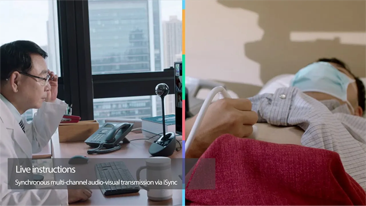

Mindray? ??? ??? ?? ??? ???? ??? ?? ??? ??? ????? ??? ????. ?? ???? ZONE Sonography? ??? ???? ?? Resona 7? ??? ZST+ ???? ?? ?? ? ?? ??? ????? ?? ??? ??? ??? ? ?? ????.